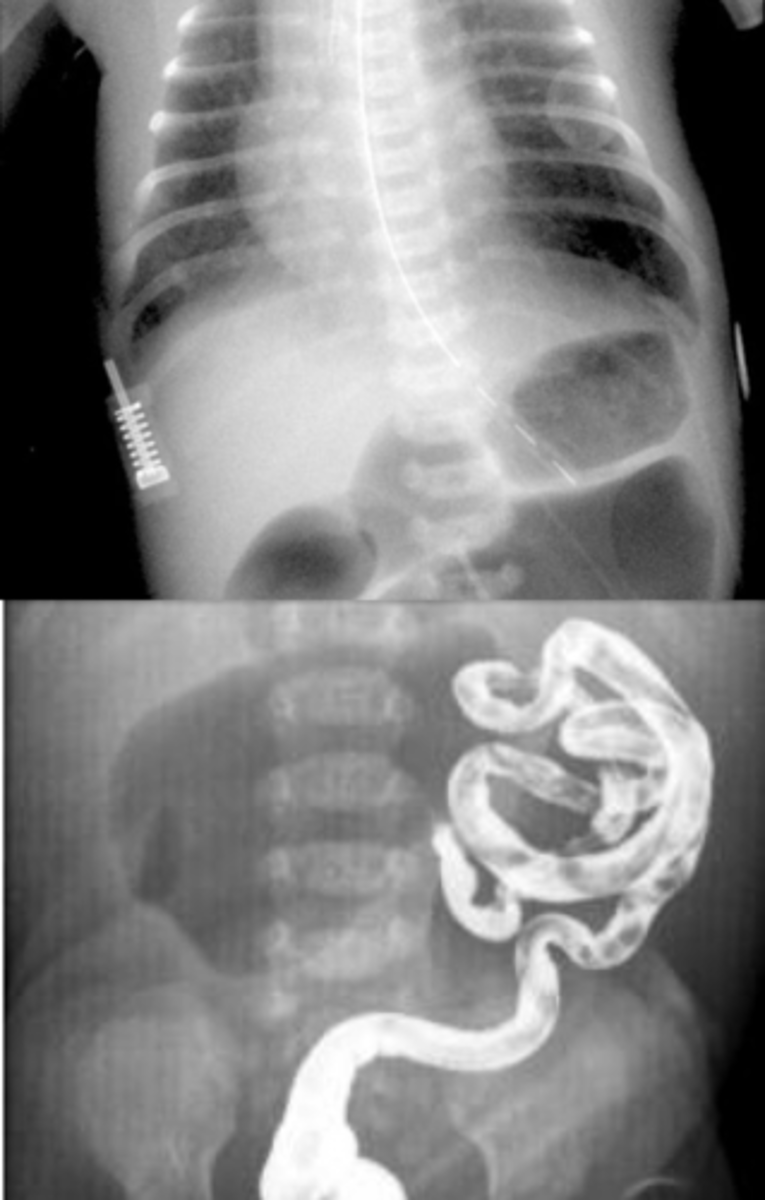

What is intestinal malrotation, & what is it often caused by?

Abnormal/incomplete rotation of the bowel during fetal development; Ladd's bands (fibrotic bands that cover parts of the small intestine)

What are the 2 major possible complications of intestinal malrotation?

Intestinal obstruction (usually due to Ladd's bands) or midgut volvulus (small bowel ischemia)

What are some s/sxs of malrotation/midgut volvulus?

Bilious vomiting, bloating, distension, fever, N/V, blood-streaked stool, acute onset of severe pain out of proportion to the PE in a previously healthy baby

What is the best initial diagnostic test for suspected malrotation/midgut volvulus, & what must this be followed up by? What will be seen?

Initial: abdominal x-ray - double bubble sign and/or air-fluid levels (remember need to d/dx duodenal atresia from this)

Best: upper GI contrast series/contrast enema - twists of barium w/ bowel pushed over to the right

How is malrotation/midgut volvulus managed?

Emergent peds consult & surgical correction (usually cut Ladd's bands & resect any dead bowel)